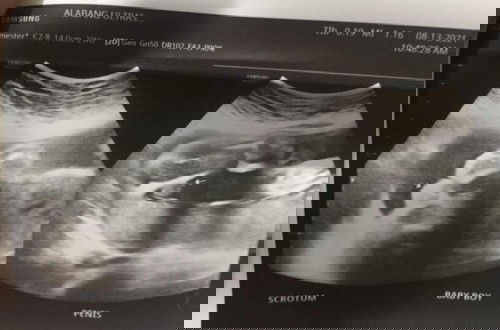

sure na po bang baby boy ang baby ko?

yes po kita namn po ang putotoy ๐Ÿ˜๐Ÿ˜